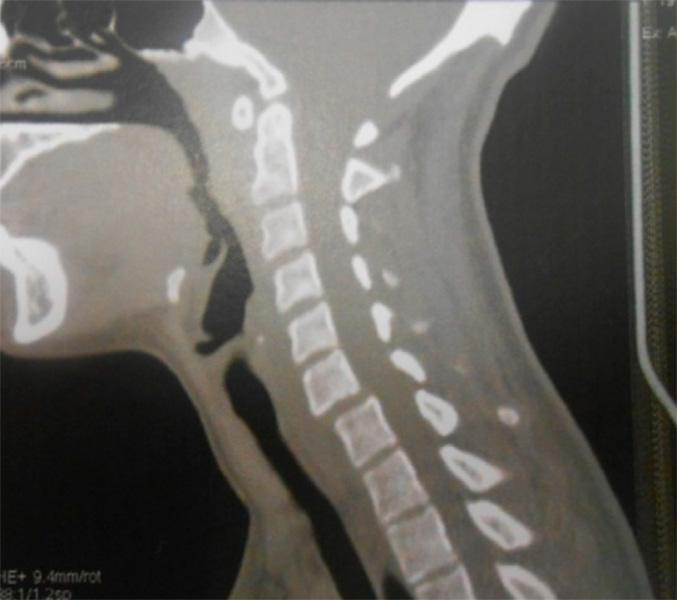

Espondilolisis Cervical: A propósito de un caso

La espondilolisis cervical se define como una hendidura del istmo vertebral o espacio existente entre las faceta superior e inferior de los pilares articulares. Mientras que a nivel lumbar se ha descrito en el 5% o 6%de la población mundial a nivel cervical se considera una anomalía rara, con menos de 100 casos publicados hasta la fecha.